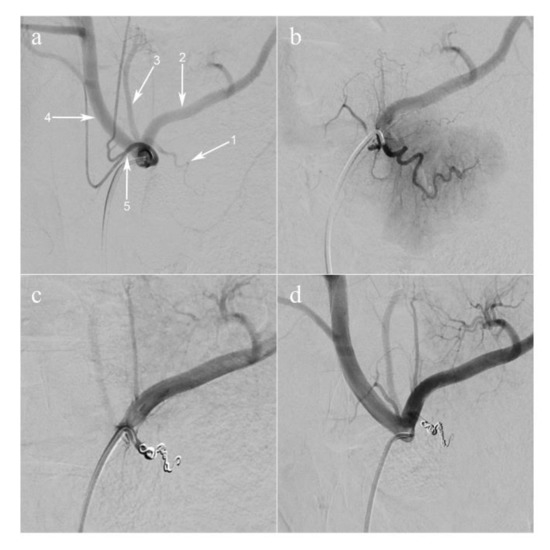

The main pancreatic branch of the splenic artery (equivalent to the dorsal pancreatic artery in humans) was selectively catheterized using a 2.8 French microcatheter (PROGREAT®, Terumo Europe NV, Leuven, Belgium). The artery was occluded using large volume 0.020-inch diameter coils (Ruby® Coils, Penumbra Inc., Alameda, CA USA), in order to obtain a selective ischemia of the pancreatic tail and part of the body ( Figure 1; Figure 2b).

Figure 1. Arterial coil embolization of pancreatic artery. (a) Selective injection of the celiac trunk (digital subtraction angiography, anteroposterior view). The dorsal pancreatic artery (1) is shown, branching off the proximal splenic artery (2); (3) the left gastric artery; (4) the common hepatic artery; (5) the common trunk of the left and right phrenic arteries. (b) Super-selective injection of the dorsal pancreatic artery. The parenchyma of the pancreatic tail is visualized. (c) The dorsal pancreatic artery is occluded with coils. (d) Selective injection of the celiac trunk post-embolization.

The endovascular procedures were successful (Figure 1) followed by imaging analyses (Figure 2a). Pancreatic ischemia could be obtained in all pigs (Figure 2b). Additionally, augmented reality (AR) of the overlaid HSI (Figure 2c) and FLER (Figure 2d) images was possible in all cases, and the virtual demarcation line between vital and ischemic zones was visually consistent in both imaging modalities (Supplementary Video). Besides, AR allowed for accurate confocal laser endoscopy (CLE) scanning, local lactate (LCL) sampling and biopsies, in correspondence with each ROI.